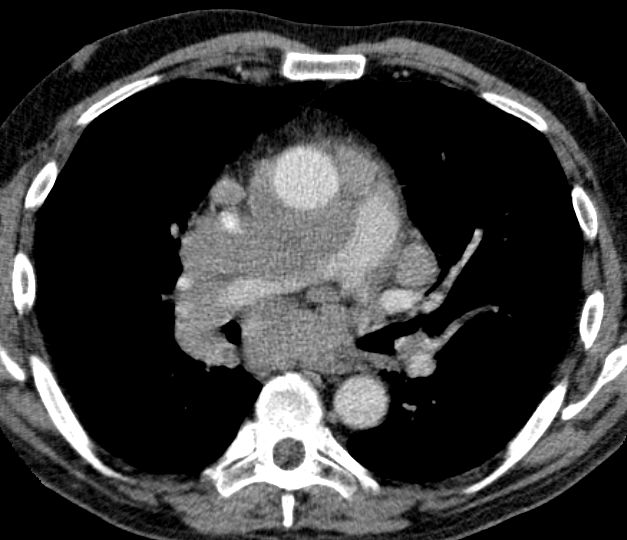

CT

Zentrales kleinzelliges Karzinom rechts. Typisch für Kleinzeller ist die fließende Ausbreitung im Mediastinum.

Kleinzelliges Karzinom des rechten Hauptbronchus mit Occlusion des Oberlappenbronchus T3 N2 M1 bra, pul,adren